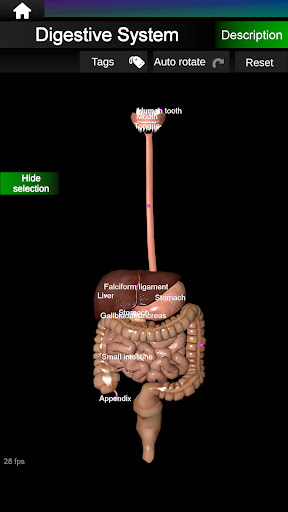

يمكنك هنا تنزيل ملف حزمة تطبيق أندرويد "Internal Organs 3D Anatomy" الخاصة بجهازVodafone Smart N9 Lite مجانًا، نسخة ملف حزمة تطبيق أندرويد - 3.4 للتحميل على Vodafone Smart N9 Lite اضغط ببساطة على هذا الزر. إنه سهل وآمن. نحن نقدم فقط ملفات حزمة تطبيق أندرويد الأصلية. إذا انتهكت أية مواد موجودة في الموقع حقوقك قم بإبلاغنا من خلال